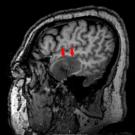

David Effron, MD; C. Clare Charbonnet, MD; Charles L. Emerman, MD; Agnieszka A. Ardelt, MD, PhD, MBA

A 66-year-old, right-handed man presented to the emergency department (ED) reporting the perception of hearing speech “in fast forward.” The perception was intermittent; episodes lasted for a few minutes...